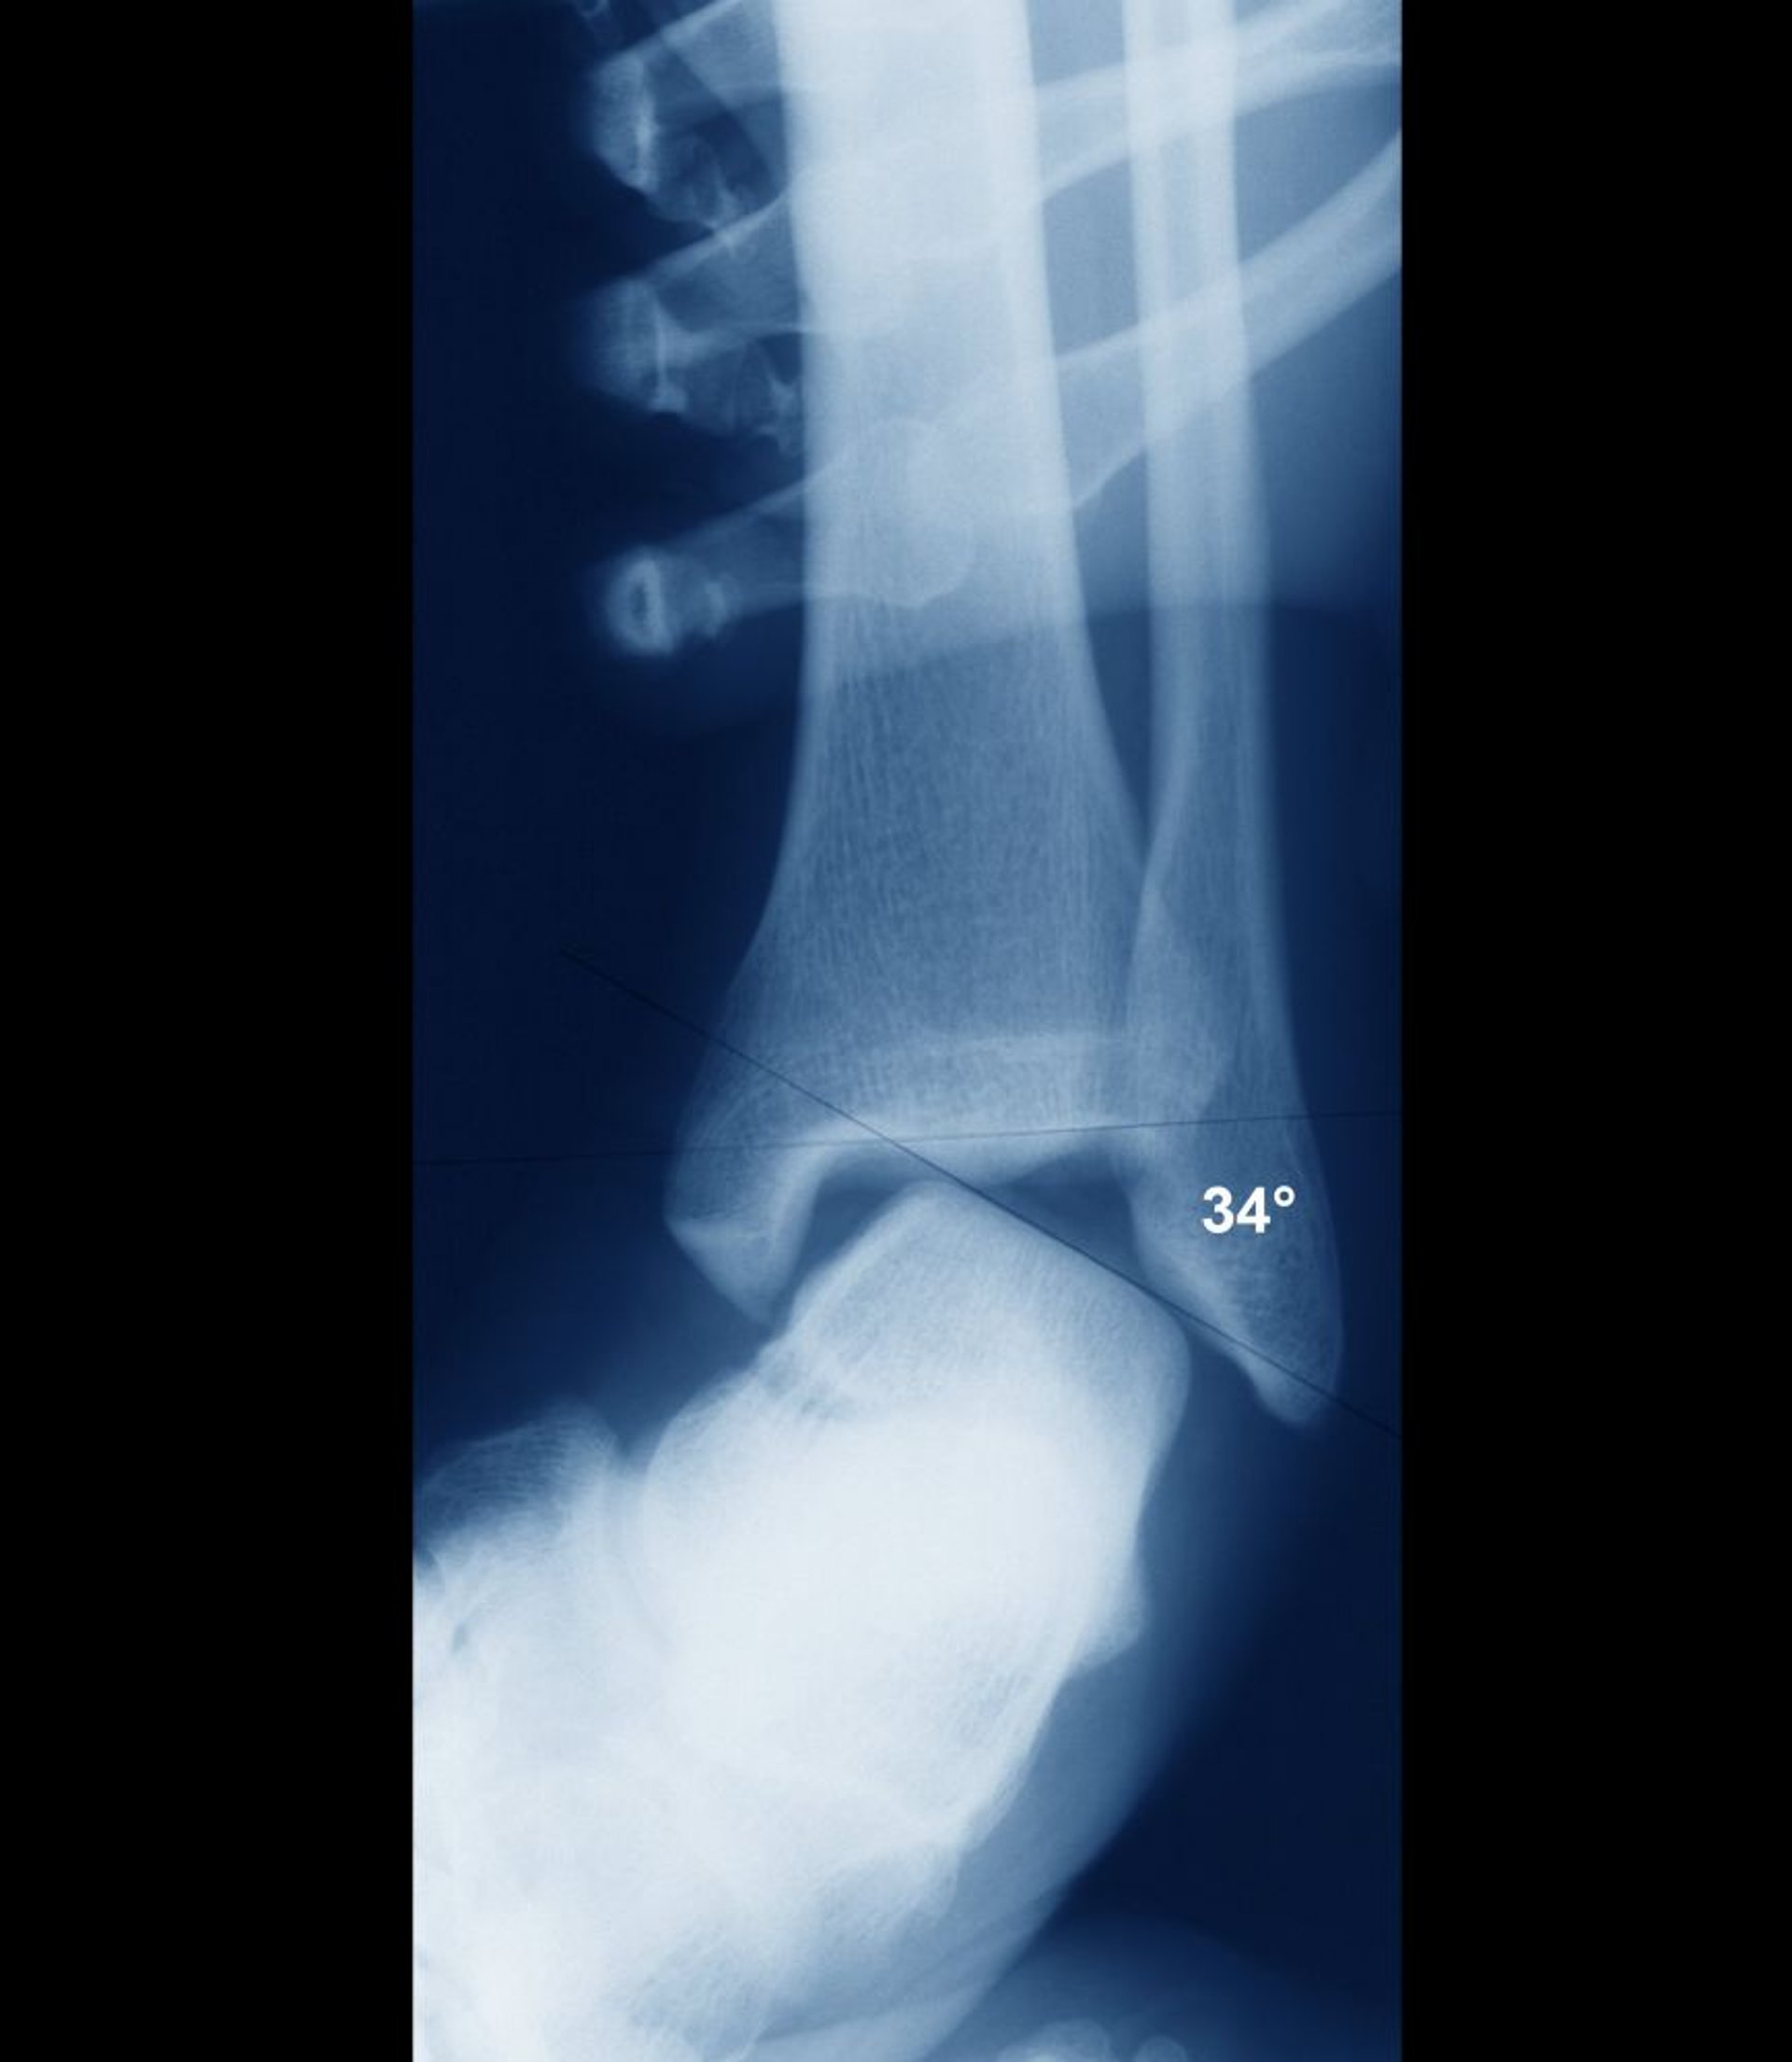

Esguince de tobillo con inestabilidad

Si el tobillo está estable, las superficies intraarticulares del astrágalo y la tibia deben ser paralelas. Aquí, están ampliamente desalineados, lo que indica una inestabilidad articular evidente. La inestabilidad se habría evidenciado con claridad en el examen clínico, y la inestabilidad normalmente se evalúa mediante el examen clínico sin necesidad de radiografías.